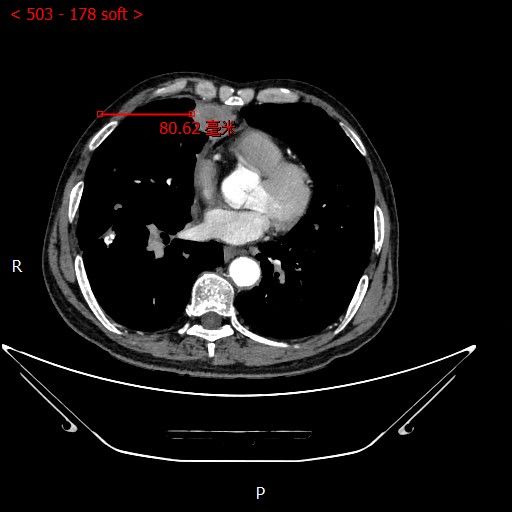

术前影像

男性患者,68岁,检查发现右肺中叶肿块,大小约3.5cm×2.4cm,因患者有慢性支气管炎、肺气肿、肺大泡,基础病较多,无法耐受常规外科手术治疗;经与患者本人及家属多次沟通。血管介入科团队根据患者具体情况决定对该患者施行CT引导下肺肿瘤射频消融术。经全科术前讨论:肿瘤位置毗邻心脏、纵膈、胸膜多处重要器官,手术要求穿刺精准,消融位置精确,尽量避免恶性心率失常,心脏包膜、胸膜、纵膈损伤。经过前期的精心术前准备,2023年7月18日,在血管介入科团队和CT室默契配合下,此次射频消融手术顺利完成。手术全过程仅用时约40分钟,其中消融时间约5分钟。CT观察下见肿瘤形变,周围肺组织呈现“晕”征,提示本次消融范围基本覆盖全肿瘤。术中患者无疼痛并且未产生并发症。本次手术达到杀死肿瘤细胞的同时,最大限度的减少创伤、保留肺组织。